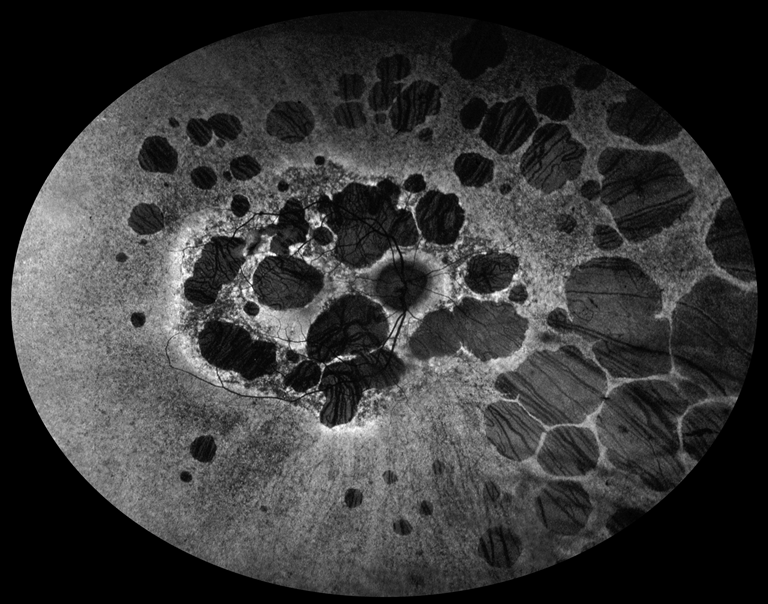

Chorioretinal Degeneration

Presented by Judith Gulian, BSc, OCT-CThis photograph received 2nd Place in the category "Fundus Autofluorescence" and was displayed at the 2024 ASCRS/OPS Society Exhibit.